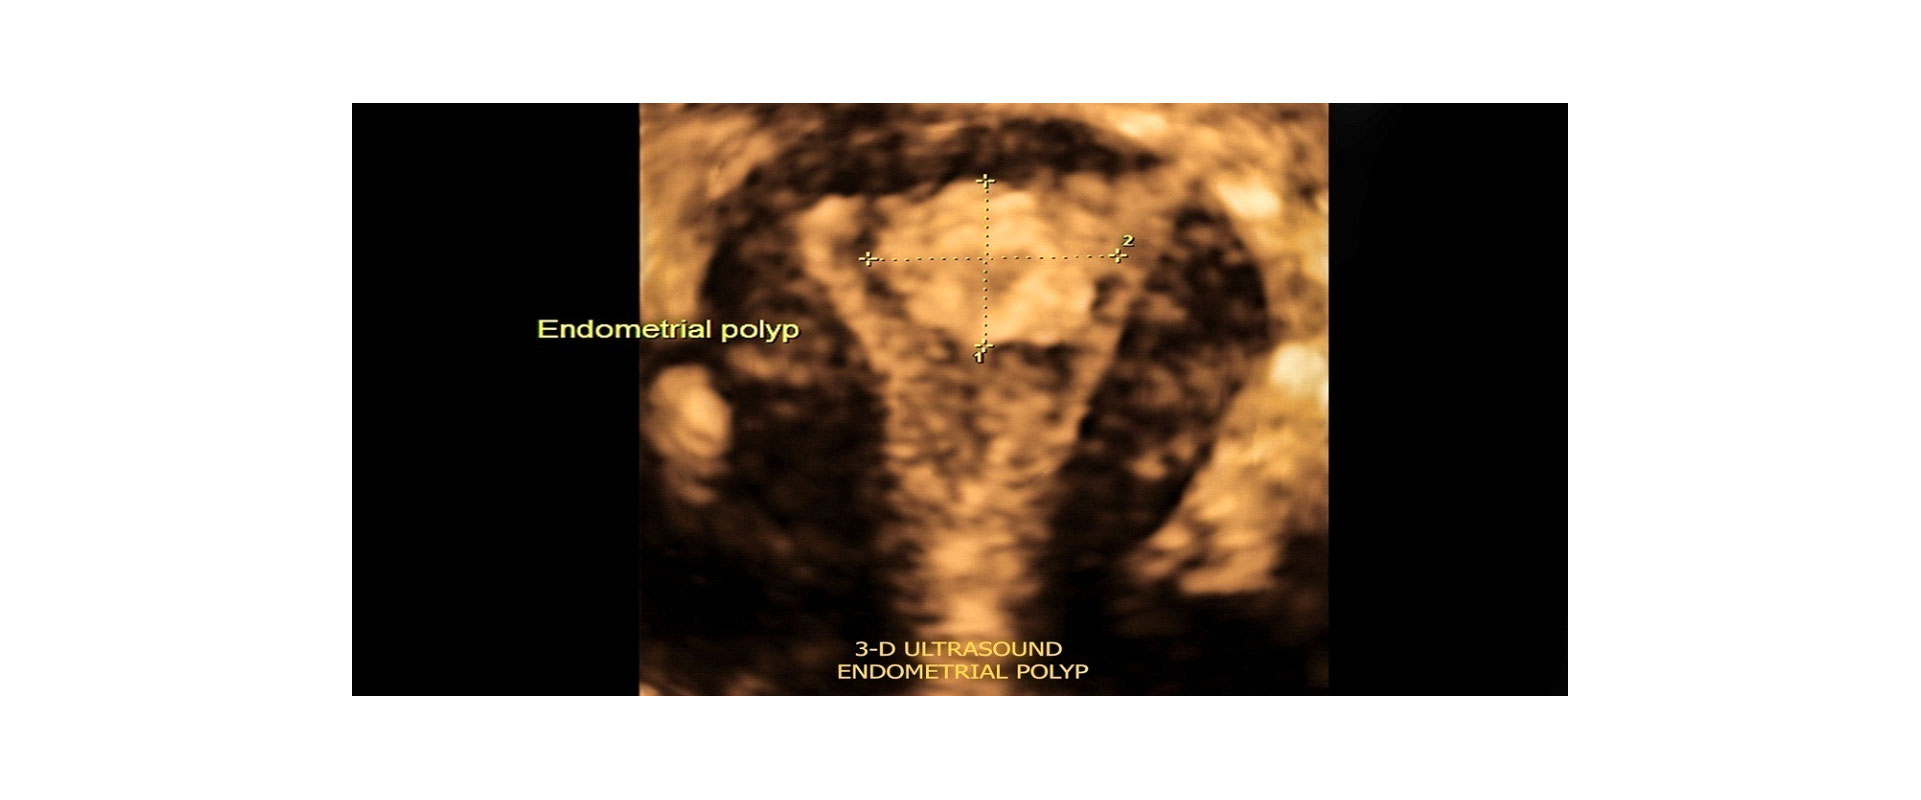

⦁ και τη φυσιολογική ανατομία της μήτρας και πιθανή παθολογία της

✓ Ακριβής Διάγνωση: Εξαιρετική ευκρίνεια εικόνων για τη διάγνωση γυναικολογικών προβλημάτων.

✓Εκτίμηση Ανατομίας: Βελτιωμένη ανάλυση της ανατομίας των γυναικείων αναπαραγωγικών οργάνων.